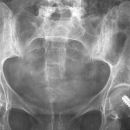

Sakroiliitis bei Bechterew